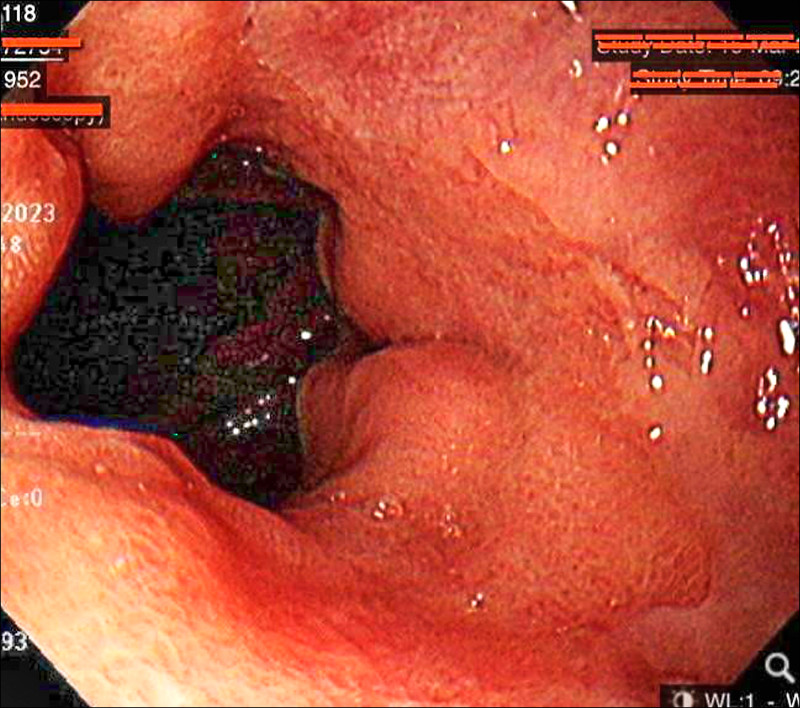

高雄阮綜合醫院胃腸肝膽消化系科醫師丁楷庭指出,人體為了抵抗寒冷低溫,會啟動血管收縮機制,將血液首先供給心臟、大腦等核心器官,以確保生命體徵,於此同時,腸胃道的血流就可能會依個人體質而減少,造成腸胃蠕動功能變差,或腸胃道免疫力下降、胃發炎等,也容易感冒或感染腸胃炎而引發腹瀉,嚴重者甚至導致胃發炎、胃潰瘍而就醫住院。

丁楷庭表示,腸胃炎患者除了「肚子著涼」外,不少患者是天冷頻繁吃麻辣鍋導致,近期門診有1對年約40歲的夫妻,雙雙因為胃酸過多、胃食道逆流就醫,一查發現兩人每週有3、4次晚餐必吃麻辣鍋物、燒烤,其中先生因有抽菸、飲酒習慣,還出現火燒心、吞嚥困難、喉嚨異物感等,症狀較嚴重。